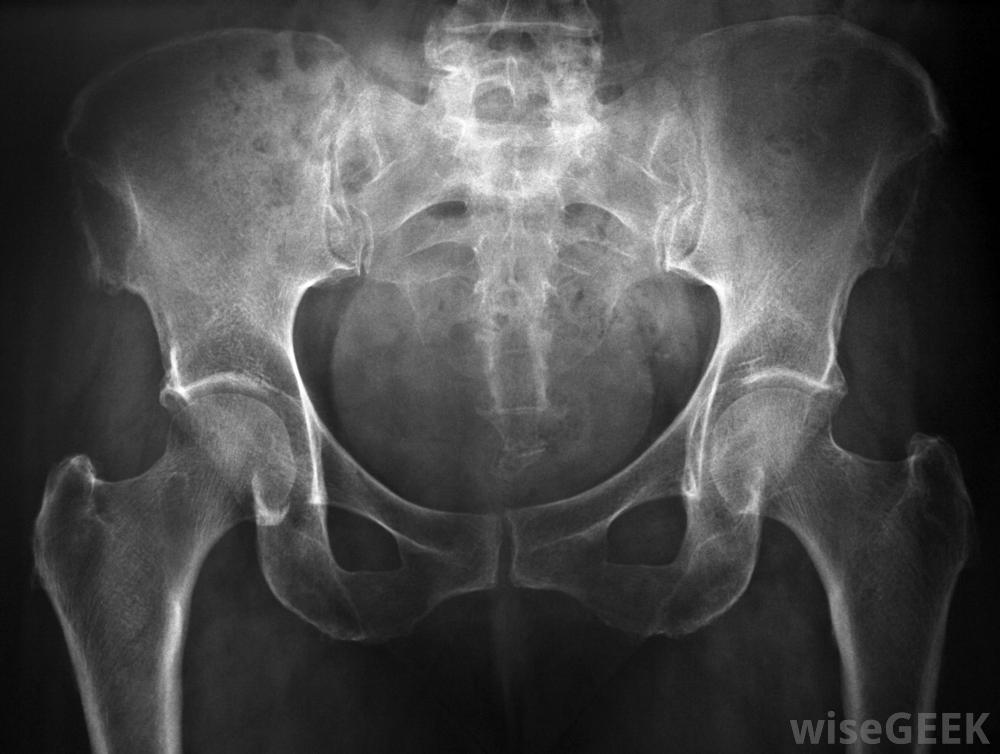

X光检查通常是用来评估髋关节的状况和检查骨骼的异常情况。目前还没有明确的病因可以导致大腿-小腿-珀斯病梅奥诊所声称,它的发展可能与二手烟暴露有关。虽然这种疾病可能会出现在两侧,也就是说它可能同时影响到两个臀部,但它通常只发生在单侧或一侧

在某些腿-小腿-珀斯病的病例中,使用拐杖来缓解跛行是适当的。在正常情况下,适当的循环为身体的各个部位提供充氧、营养丰富的血液在Legg-Calve-Perthes病的病例中,原本供应髋关节的血液循环受损,髋关节内缺乏血液的细胞立即开始死亡。骨细胞的死亡导致骨骼退化,使受累的骨物质受损,即使是新的,健康的细胞到达。由此导致的髋关节不稳定使其容易骨折,无法正常愈合。Legg-Calve-Perthes病可能在儿童时期的任何时候被诊断出来,但最常见的是在孩子出生后的第二年发现。疾病越早被发现,孩子的预后越好。经过全面的会诊和身体检查,通常会进行一系列的影像学检查。经常进行骨骼扫描和X光检查来评估儿童的状况检查髋关节是否有异常或骨改变。患有腿-小腿-珀斯病的儿童通常会表现出跛行并抱怨患侧疼痛。限制运动范围导致僵硬的情况并不少见一些儿童可能会说,休息或不活动关节可以减轻疼痛。久而久之,儿童跛行会导致患肢肌肉收缩。如果忽视了腿-小腿-珀斯病的症状或延迟治疗,髋关节可能会出现永久性损伤治疗Legg-Calve-Perthes病的核心是防止对髋关节的永久性损伤,抗炎药通常用于减轻炎症和缓解不适虽然在某些情况下使用拐杖来缓解跛行可能是适当的,但在其他情况下,可能需要使用支架固定骨骼。也可以进行手术来纠正肌肉收缩或调整髋关节Legg-Calve-Perthes病是一种影响髋关节的疾病。